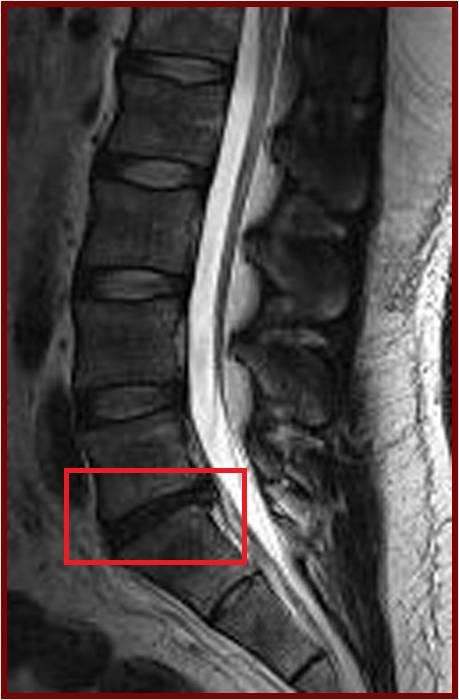

The current study was a cross-sectional assessment of adults from this cohort who were 21 years of age and older. A total of 2,599 individuals were assessed with magnetic resonance imaging (MRI). Amongst them, 27% (n=709) did not have disc degeneration while 73% (n=1,890) had. Of the subjects who have disc degeneration, 7% were underweight, 48% were in the normal weight range, 36% were overweight, and 9% were obese. Overweight and obese individuals were also found to have a greater extent and severity of disc degeneration in comparison to those individuals of normal weight or underweight.